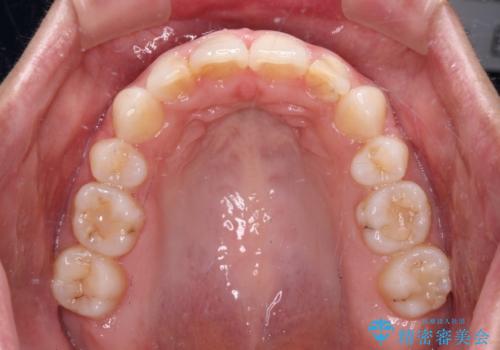

- くちばしのような前歯の突出感を気にして来院された患者様です。

上下左右第一小臼歯4本を抜歯して、積極的に口元を引っ込めるよう、ワイヤー装置にて矯正治療を行うこととしました。

抜歯矯正を行ったことで、顎先のつっぱり感や口元の閉じにくさを解消することができました。